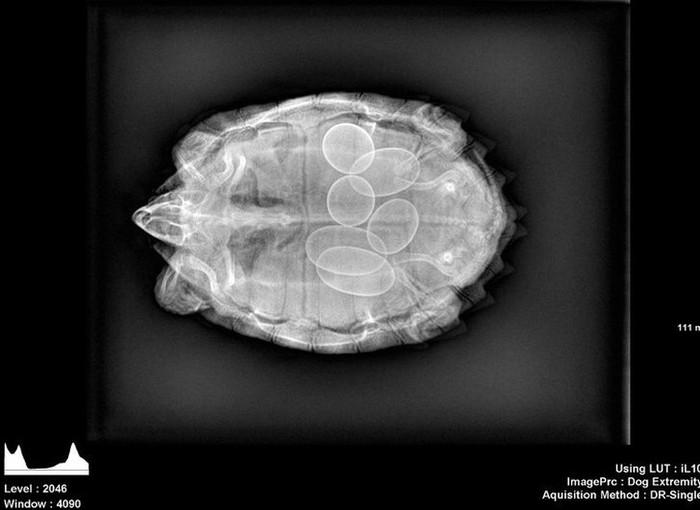

Penampakan dalam tubuh penyu saat hamil. (Foto: Brightside)